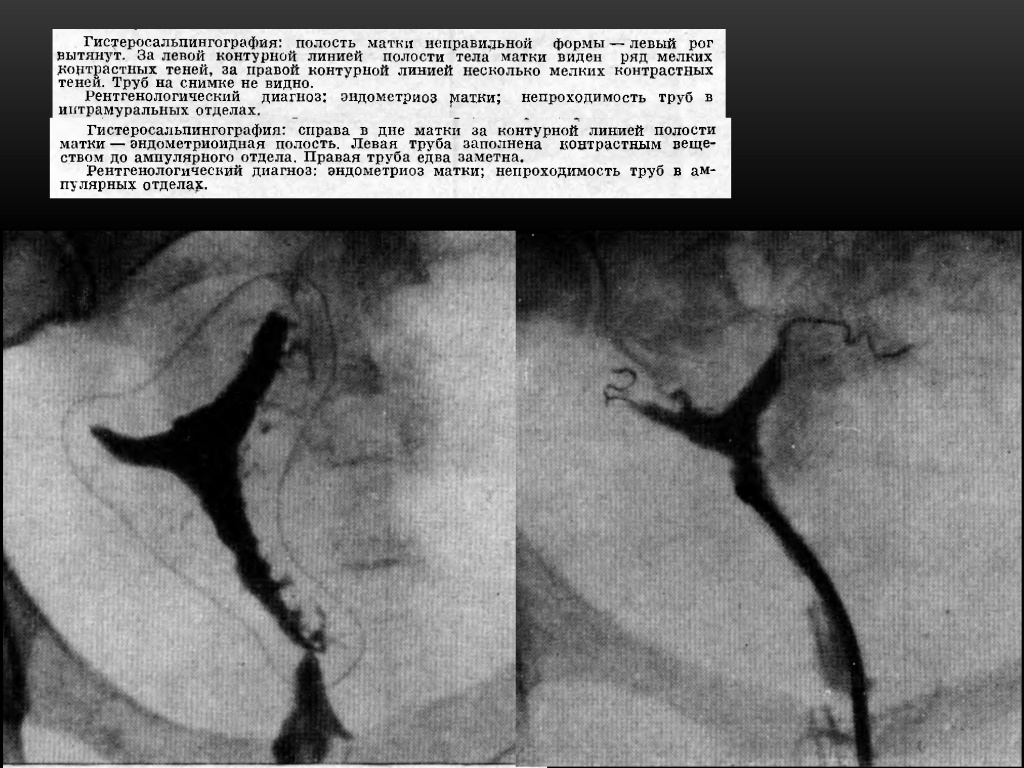

Гистеросальпингография: описание и фотографии